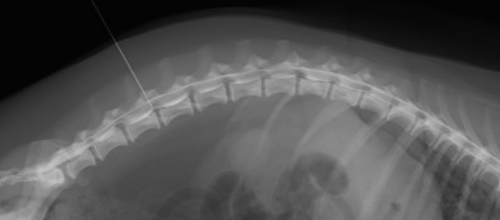

- 脊髄造影レントゲン撮影

- 経済的な理由、もしくは飼い主様のご希望でMRI・CT撮影をしない場合に手術に先駆けて行う検査が脊髄造影レントゲン検査です。(診断率90%以上)